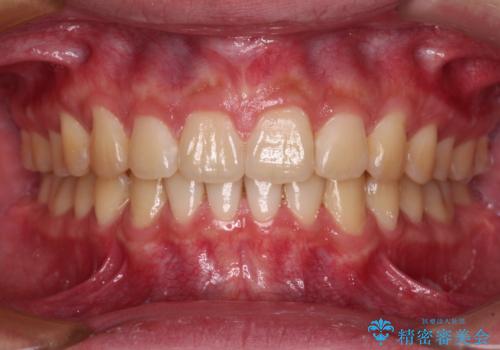

舌の突出癖により上下前歯が開咬となりましたが、舌のトレーニングと顎間ゴムの使用により、元々の被蓋関係に改善することができました。

アンカースクリューを用いて、出っ歯仕上がりを回避し、正中位置も改善することができました。